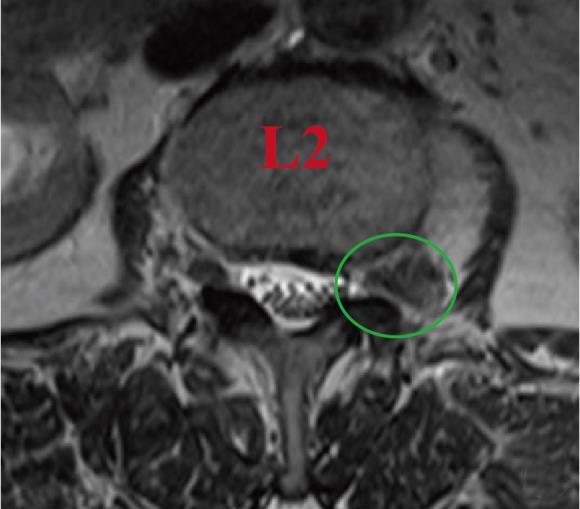

• 单通道非同轴脊柱内镜经椎间孔外入路(椎板外切迹)治疗极外侧椎间盘突出症的临床疗效观察

2026, 32(3):28-36. DOI: 10.12235/E20250050

摘要 (43) HTML (65) PDF 6.88 M (47) 评论 (0) 收藏

摘要:目的 观察单通道非同轴脊柱内镜经椎间孔外入路(椎板外切迹)治疗极外侧椎间盘突出症(FLLDH)的临床疗效。方法 回顾性分析2022年5月-2024年5月该院收治的,行单通道非同轴脊柱内镜经椎间孔外入路(椎板外切迹)治疗的FLLDH患者70例。于术前和术后,评估腰腿疼痛程度、腰椎功能和临床疗效。结果 相较于术前,术后3 d和3个月,患者下肢视觉模拟评分法(VAS)评分、腰部VAS评分、Oswestry功能障碍指数(ODI)、数字分级评分法(NRS)评分和Roland-Morris功能障碍问卷(RMDQ)评分明显降低,日本骨科协会(JOA)评分明显升高,差异均有统计学意义(P < 0.05);改良MacNab评分标准显示,末次随访时的优良率为94.28%。结论 单通道非同轴脊柱内镜经椎间孔外入路(椎板外切迹)治疗FLLDH,能明显改善患者腰腿疼痛和腰椎下肢功能,其具有创伤小、易操作、安全性高和疗效好等优点,值得在临床推广应用。